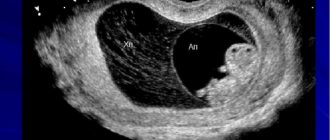

На узи не видно эмбриона: причины Когда наступает долгожданная беременность, оплодотворенная яйцеклетка опускается в

Внутриутробное развитие эмбриона. Сроки появления и нормы сердечного ритма Внутриутробное развитие эмбриона начинается с